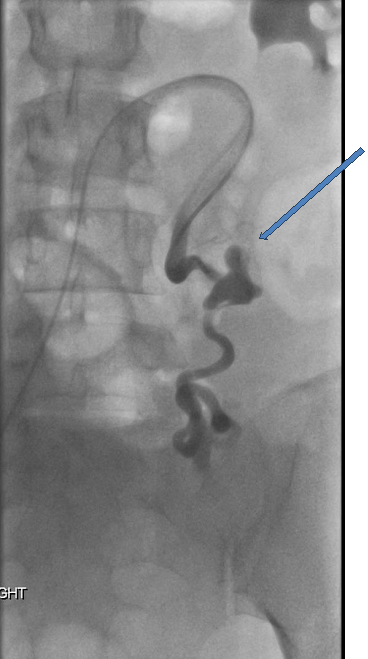

Interventional Radiology (IR) consultation was obtained and CT-guided angiography of the abdomen and pelvis was performed which demonstrated a markedly dilated, tortuous left ovarian artery with a 2.5 cm pseudo-aneurysm at the proximal to mid portion, and adjacent contrast extravasation into the retroperitoneum. At the same time, percutaneous embolization was performed using 6, 8, and 10 mm nester embolization coils as well as Gelfoam slurry (Figure 3A & 3B). Gynecologic oncology consultation was also obtained, and the decision was made not to perform a laparotomy, but to observe for further evidence of ongoing bleeding.

Figure 3A Abdominal aortogram and selective left ovarian artery angiogram demonstrating 2.5 cm pseudo-aneurysm of proximal to mid portion of the ovarian artery with adjacent contrast extravasation/hematoma.